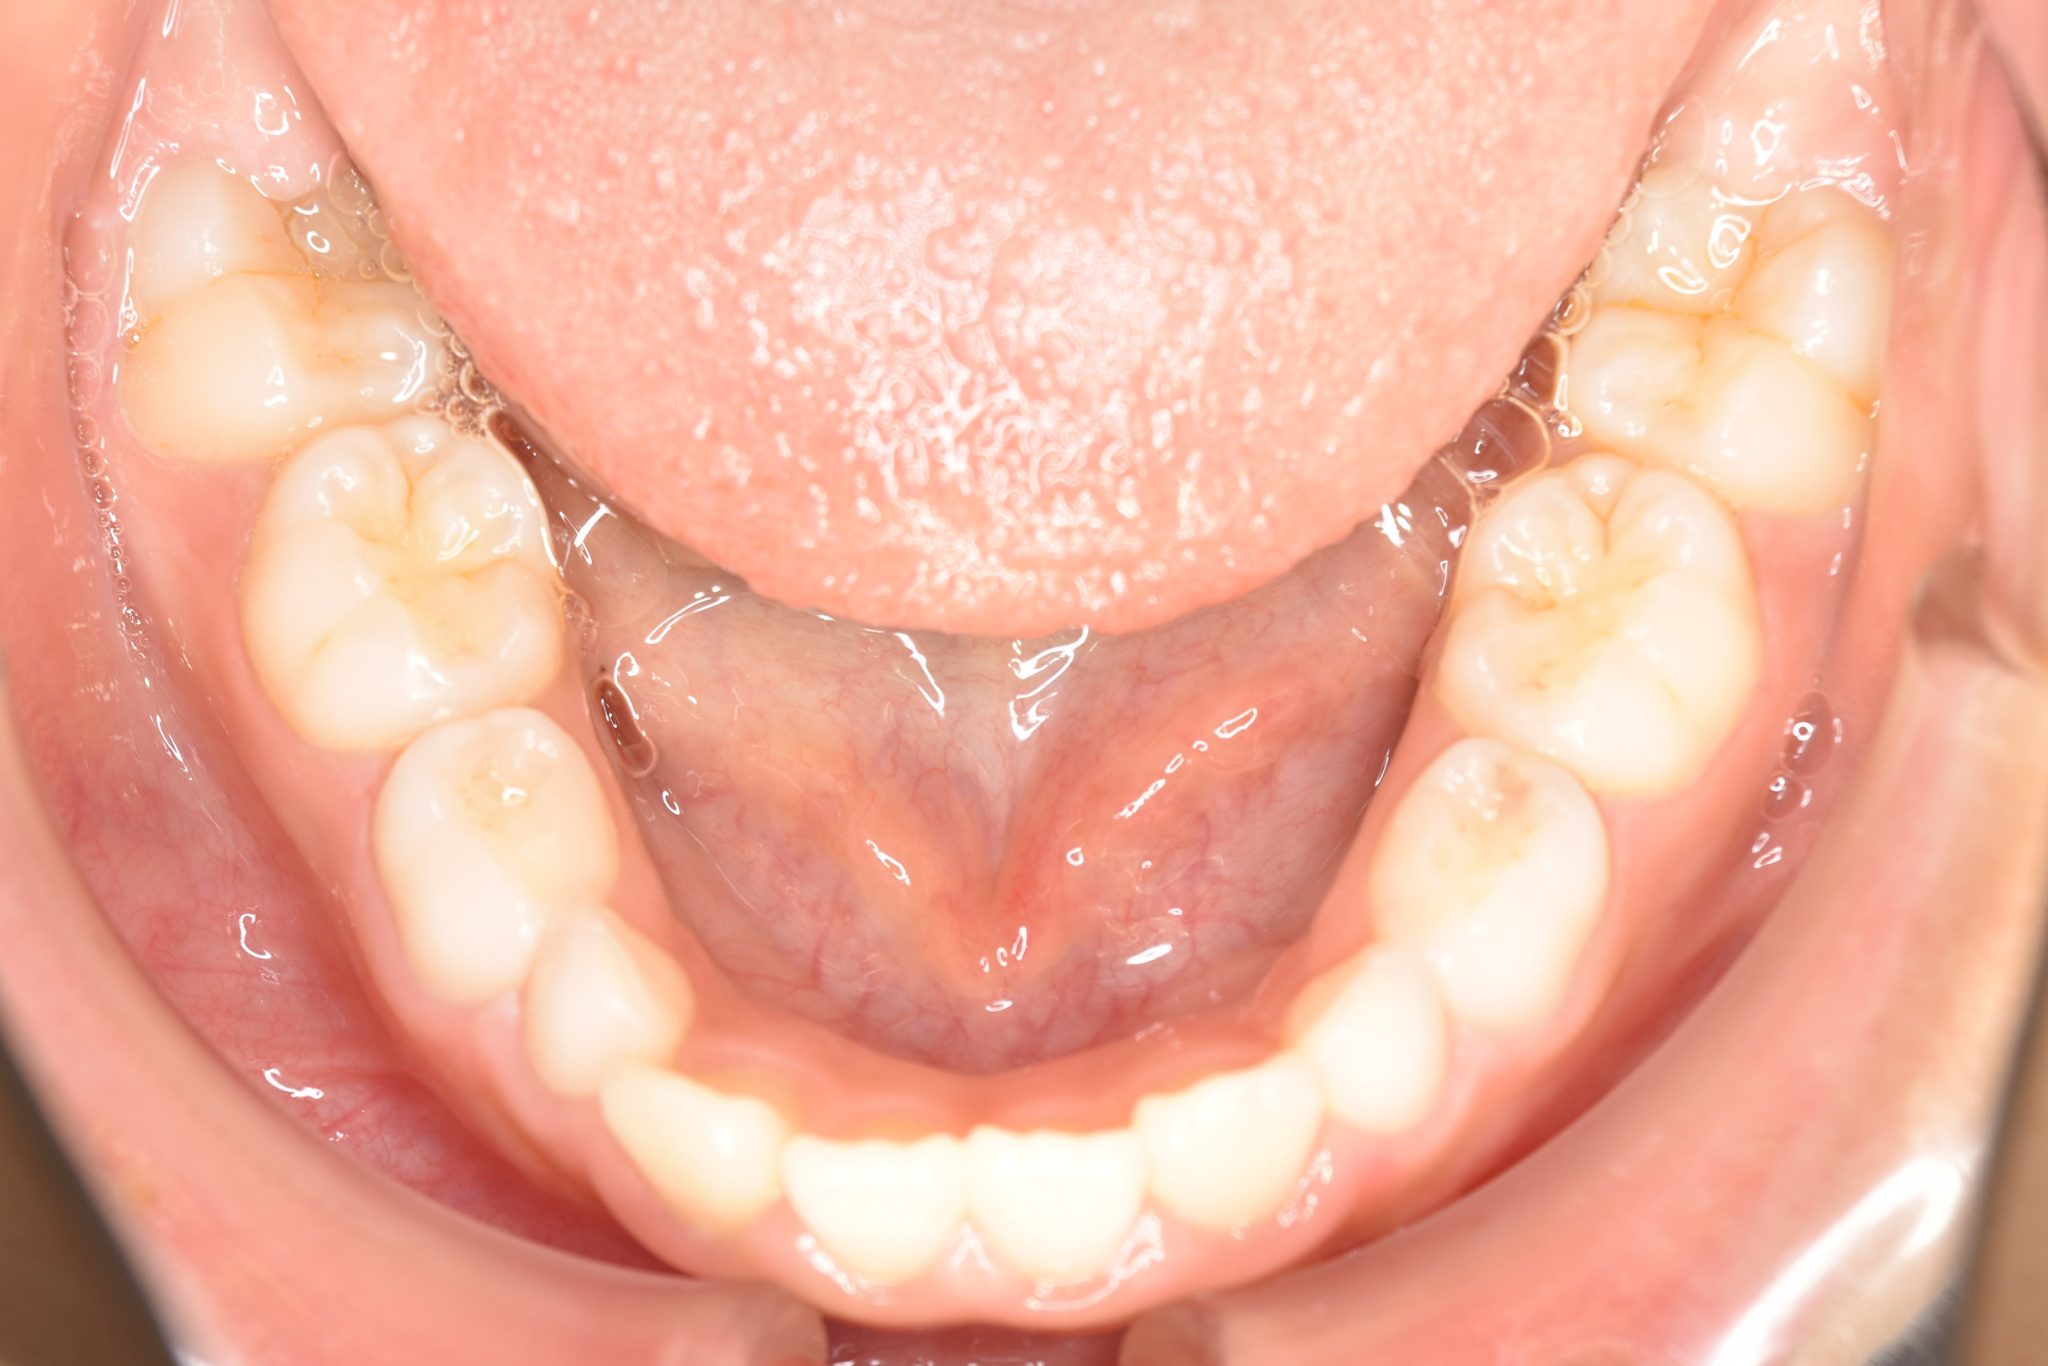

子どもの矯正治療|症例_547

主訴 上下の歯が接触しない

施術内容 上顎急速拡大装置と下顎リンガルアーチを用いて上下顎骨を拡大した。

その後マウスピース型矯正装置で歯牙を配列し良好な咬合を獲得した。